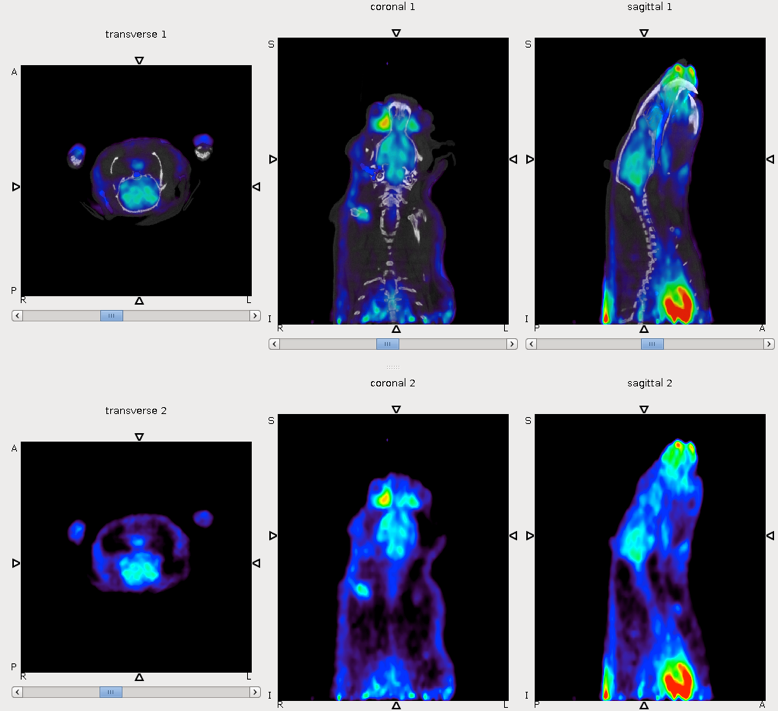

CASE 1: Mouse dynamic PET imaging for quantification of tracer uptake

• Courtesy of: D.Panetta and P.A. Salvadori, IFC-CNR Pisa, Italy

Research objective: Quantification of tracer uptake in different organs in a PET dynamic imaging

Animal model: Obese mouse (B6;129)

Acquisition protocol: 30 min acquisition time, 1 bed position

Processing and reconstruction protocol: Framing setup: 8x5” + 8x10" + 3x40" + 2x60" + 2x120" + 2x300" 3D-OSEM, 0.855 mm isotropic voxel size

Biomarker or contrast agent: Bolus injection of 18F-FDG, 6 MBq